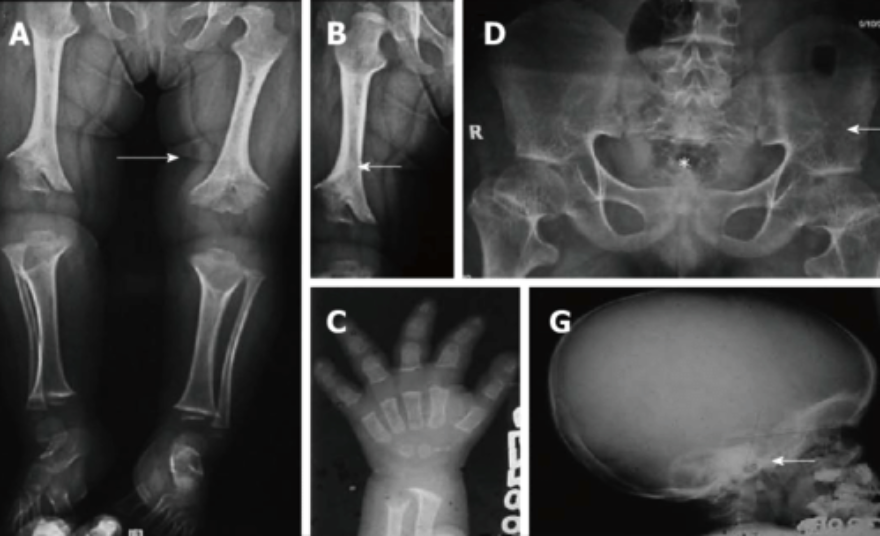

Radiografie Preventive Per La Diagnosi Precoce Delle Malattie Genetiche Michele D Amato Ortopedia Veterinariamichele D Amato Ortopedia Veterinaria

Radiografie Ufficiali Anca E Gomito Clinica Veterinaria Galilei